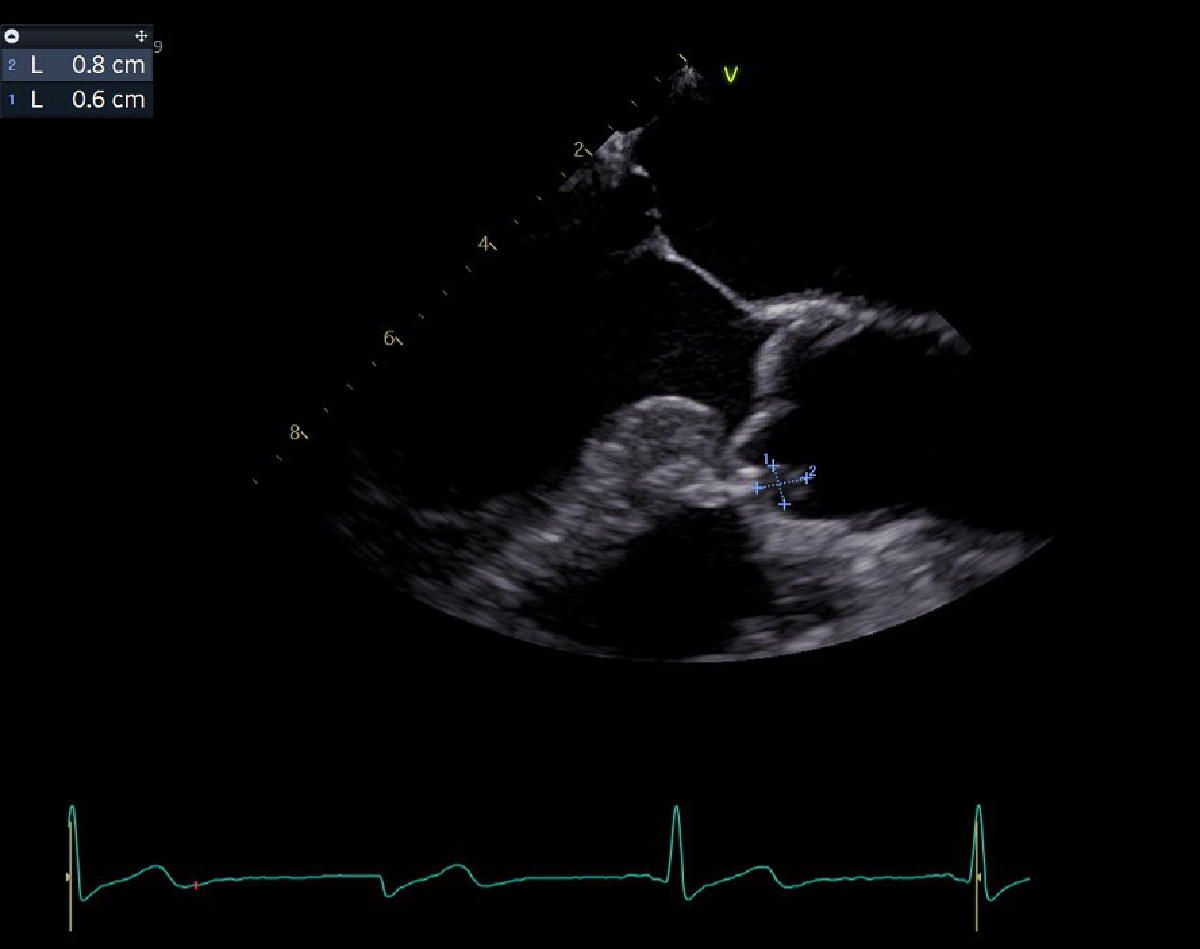

Clinical examination revealed Janeway lesions and Osler nodes (figures 1 and 2) and possibly splinter haemorrhages, which were difficult to assess due to dry and brittle nails. Transoesophageal echocardiography showed a vegetation on the aortic valve (on the right coronary cusp, sized 8 × 6 mm) and changes of the mitral and tricuspid valve suggestive of involvement of these valves (figure 3). Laboratory results showed a slightly elevated CRP (25 mg/l) with a normal white blood cell count. Due to initial suspicion of recurrent S. aureus endocarditis, antibiotic therapy with co-amoxicillin 2.2 g quad 4 h was initiated upon admission.

Figure 3Transoesophageal image of vegetation.